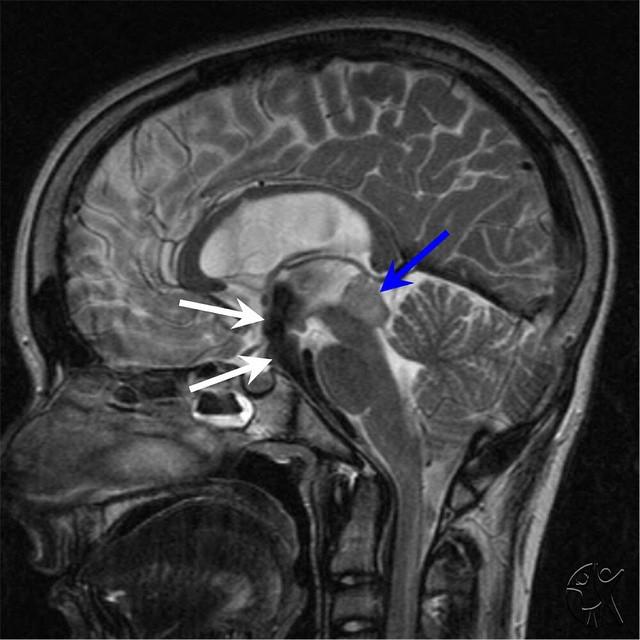

Computed Tomography Of The Head - Wikipedia, The Free ...

Computer tomography of human brain, from base of the skull to top. Taken with intravenous contrast medium. ... Read Article